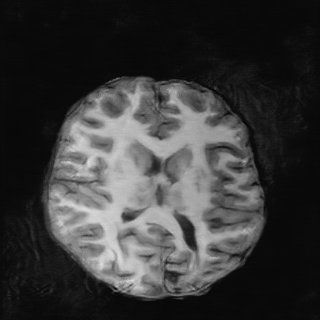

Tomographic image reconstruction is generally an ill-posed linear inverse problem. Such ill-posed inverse problems are typically regularized using prior knowledge of the sought-after object property. Recently, deep neural networks have been actively investigated for regularizing image reconstruction problems by learning a prior for the object properties from training images. However, an analysis of the prior information learned by these deep networks and their ability to generalize to data that may lie outside the training distribution is still being explored. An inaccurate prior might lead to false structures being hallucinated in the reconstructed image and that is a cause for serious concern in medical imaging. In this work, we propose to illustrate the effect of the prior imposed by a reconstruction method by decomposing the image estimate into generalized measurement and null components. The concept of a hallucination map is introduced for the general purpose of understanding the effect of the prior in regularized reconstruction methods. Numerical studies are conducted corresponding to a stylized tomographic imaging modality. The behavior of different reconstruction methods under the proposed formalism is discussed with the help of the numerical studies.